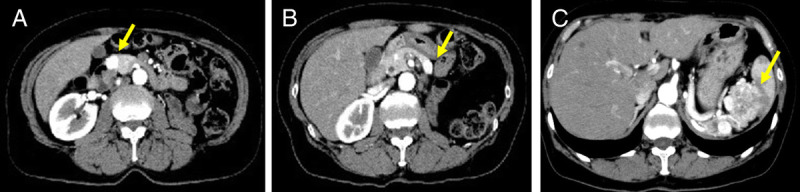

Contrast-enhanced harmonic EUS with time-intensity curve analysis useful for diagnosis of pancreatic metastasis from renal cell carcinoma (with videos).

对比增强谐波 EUS 与时间强度曲线分析有助于诊断肾细胞癌的胰腺转移(附视频)。